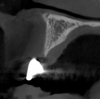

After 3 months of post-orthodontic stabilization, a cone-beam computed tomography scan was taken to re-evaluate the results and plan the future treatment sequence. Tomographic images clearly showed vertical gains in alveolar height, including in the edentulous area corresponding to tooth No. 7 (Figure 10 through Figure 12). The apex of tooth No. 8 was forced-erupted beyond its socket and could be visibly located within the soft tissue.30,33

Fig 10. Tomographic images of teeth Nos. 6 (Fig 10), 7 (Fig 11), and 8 (Fig 12) clearly showed vertical gains in alveolar height, including in the edentulous area corresponding to tooth No. 7. The apex of tooth No. 8 was located within the soft tissue because it was force-erupted beyond its socket.

Figure 10